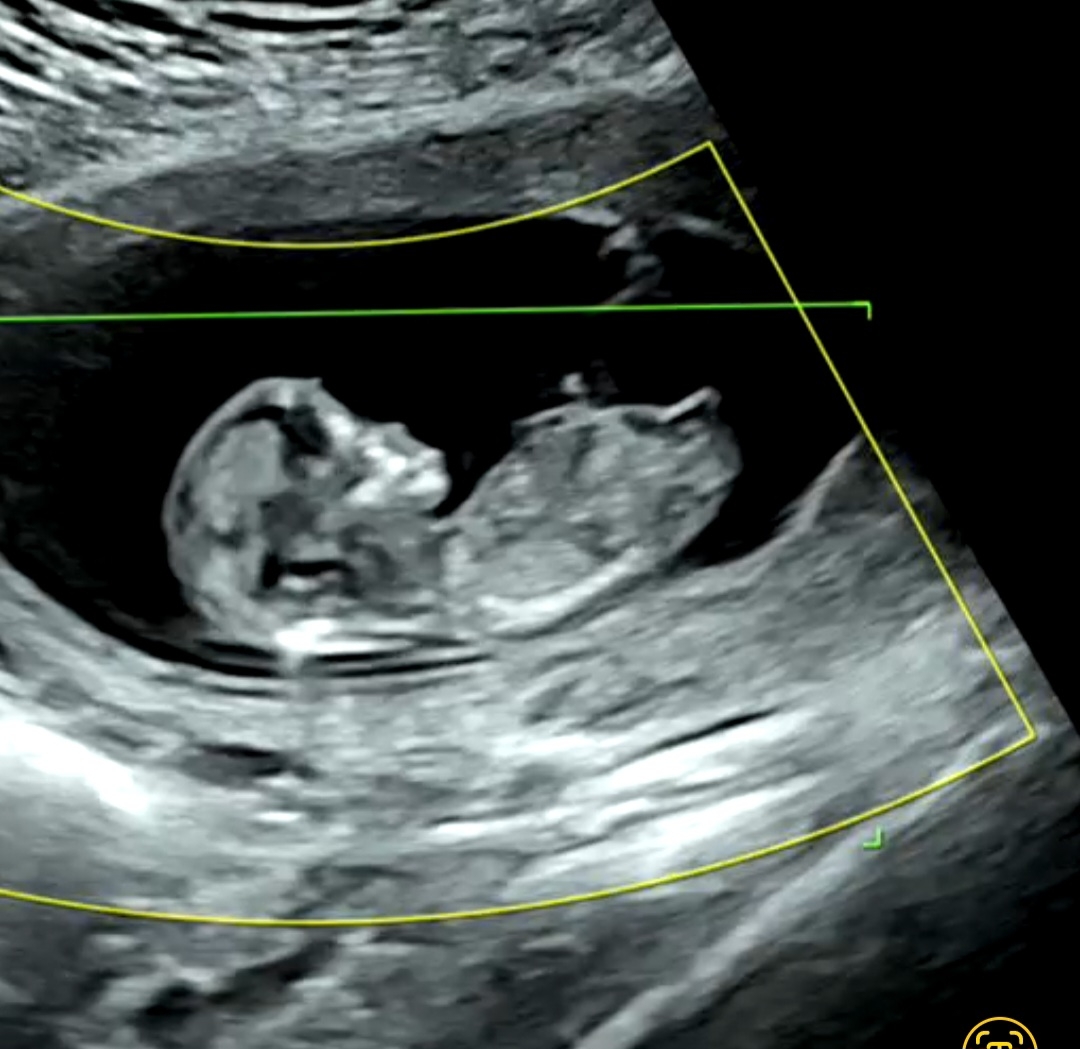

12주 1일 각도법 반전 확률

제가 보기엔 딸 같은데.. 12주 이후 반전 확률이 높을까요?